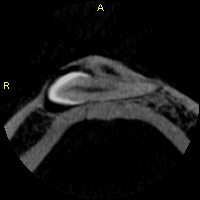

Ethmoid bone lesion in a young girl. Your diagnosis? What are these stunning concentric ring structures??? Answers & more pics: kikoxp.com/posts/10498. Thx to @ConnorZuraski for sharing this case with me! #BSTpath #pathologists #pathology #pathTwitter #oralpath #dental #dentist